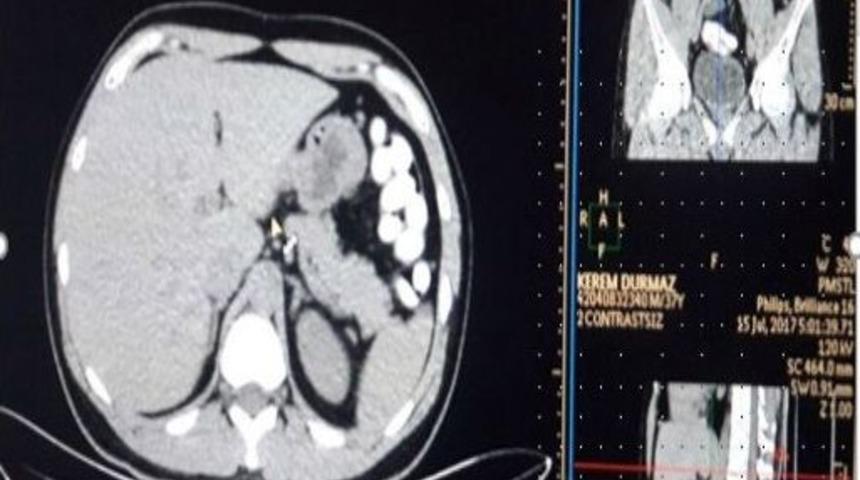

Sabiha Gökçen Havalimanında, Faslı uyuşturucu kuryesinin sindirim sisteminden 78 adet kapsül esrar çıkarıldı. Sindirim sistemindeki esrar kapsülleri, çekilen MR’da ortaya çıkarıldı.Edinilen bilgiye göre, İstanbul Emniyet Müdürlüğü Narkotik Suçlarla Mücadele Şube Müdürlüğü ekipleri, Fas’ın başkenti Kazablanka’dan uyuşturucu madde getirileceği bilgisi üzerine çalışma başlattı. Polis, 15 Temmuz Cumartesi günü Sabiha Gökçen Havalimanında risk analizi yöntemiyle yaptığı çalışmalarda Kazablanka’dan K.D.’yi (37) havalimanında gözaltına aldı.Mideden kapsül içinde uyuşturucu çıktıPolis ekipleri, uyuşturucu taşıdığından şüphelendiği D.K.’nin valizinde yapılan aramalarda içinde esrar bulunan çok sayıda kapsül ele geçirdi. Şüphelinin uyuşturucu maddenin bir kısmını kapsül halinde yutmuş olabileceğini değerlendiren polis, şüpheliyi hastaneye götürdü. Hastanede sindirim sistemi röntgen filmi ile kontrol edilen şüphelinin midesinde esrar maddesi olduğu değerlendirilen 78 kapsül ortaya çıktı. Uyuşturucu polisi tarafından emniyetteki sorgulanması tamamlanan Fas uyruklu D.K., dün adliyeye sevk edildi. Şüpheli D.K., çıkarıldığı mahkemece tutuklanarak cezaevine gönderildi.